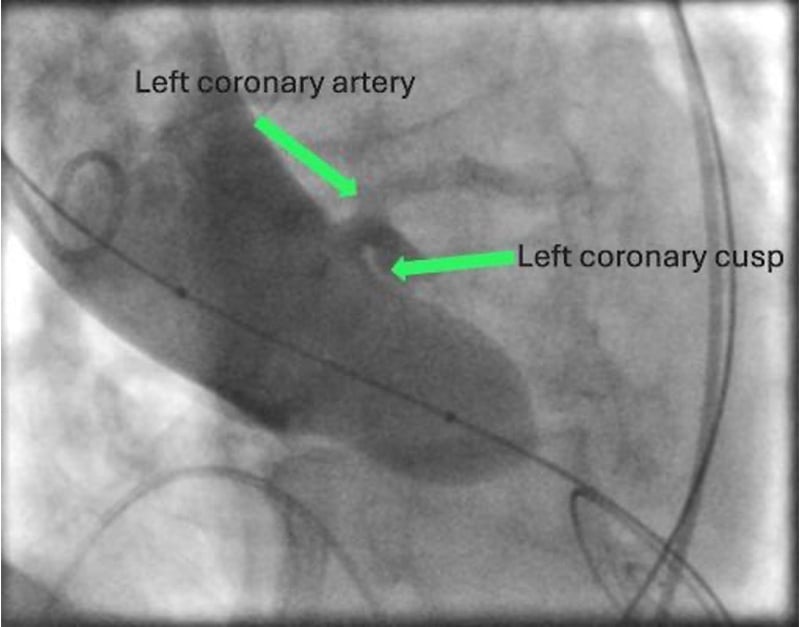

Anschließend wurde das korrekte Crimpen der Navitor Vision 25 mm unter Durchleuchtung überprüft. In einer C-Bogen-Angulation mit Exposition des LCA Ostiums (LCA-view: LAO 31 CRA 10) erfolgte eine Prädilatation der nativen Aortenklappe mit einem 20 mm semi-compliant Ballon (VACS III) unter ventrikulärer Schrittmacherstimulation (180-200/min). Während der vollständigen Balloninflation erfolgte eine Aortographie, die eine ausreichende Distanz zwischen der linken Taschenklappe und dem LCA Ostium zeigte. Die Länge der linkskoronaren Tasche erscheint kürzer als der Abstand des Anulus zur Koronararterie (Abbildung 8, Video 1).

Abbildung 8: Ballonprädilatation der Aortenklappe in "LCA-Ansicht"

Die Verwendung der "S-Kurve" der Annulusebene zur Identifizierung von Projektionen, die orthogonal zum Ostium der Koronararterien verlaufen, ist bei der Beurteilung des intraprozeduralen Risikos einer Koronarobstruktion hilfreich, da so die Ausdehnung der Taschenklappen während der Valvuloplastie und der simultanen Aortographie dargestellt werden können.

Dr. Gonska und ihr Team führten den Eingriff entsprechend bestens klinischer Empfehlungen durch und fokussierten die spezifischen Herausforderungen: Um das Risiko einer Koronarobstruktion zu beurteilen, wurde eine Valvuloplastie mit gleichzeitiger Aortenwurzelangiographie in einer anhand der CT bestimmten C-Bogen-Angulation durchgeführt, um das LCA Osmium optimal zu darzustellen (LCA-Projektion). Die Navitor Prothese wurde in cusp-overlap-Projektion implantiert, um eine optimale Implantationstiefe im Bereich des non-koronaren Sinus zu erreichen und damit das Risiko von Leitungsstörungen zu minimieren. Durch bewusst langsames Freisetzen konnte eine stabile Position der Katheterklappe bis zur vollständigen Implantation erzielt werden. Ein paravalvuläres Leck (PVL) wurde erfolgreich durch Dilatation der Aortenklappenprothese behandelt, wobei aufgrund aufgrund der Annulusverkalkungen zunächst ein 20 mm und in der Folge ein 22 mm)´gewählt wurde. Final bestand ein geringgradiges PVL, invasiver Ausschluss eines Gradienten über die Aortenklappenprothese.

Die Fallpräsentation unterstreicht die Bedeutung einer dezidierten CT-Analyse zur Identifizierung spezifischer anatomischer Besonderheiten und zur Bestimmung der C-Bogen-Angulationen für eine optimale Visualisierung der prozedurrelevanten Strukturen. Neben der, insbesondere für die Implantation von selbstexpandierenden Transkatheterklappen etablierten cusp-overlap-Projektion, wurde in diesem Fall eine LCA-Projektion verwendet, um die räumliche Nähe zwischen nativem linkskoronaren Aortenklappensegel und dem LCA Ostium während der Valvuloplastie, die unter simultaner Aortenwurzelangiographie durchgeführt wurde, zu beurteilen.